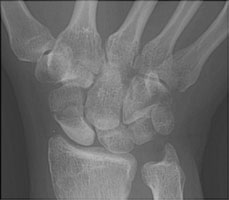

- Click on the image for a larger versionAPA radiograph of the wrist with scaphoid deviation. This view shows a fracture of the waist of the scaphoid bone.